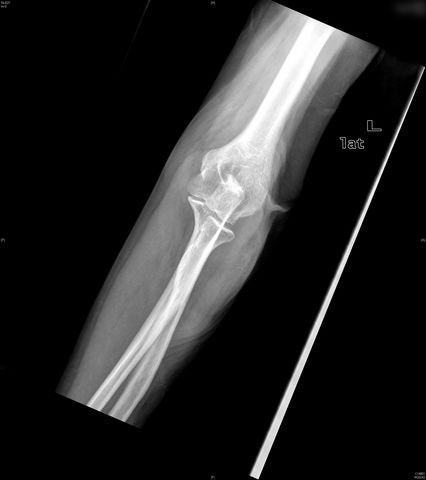

Fractura supracondílea de codo.

Fractura supracondílea de codo.Tras reducción y osteosíntesis.

Fractura supracondílea de codo. Tratamiento con agujas.